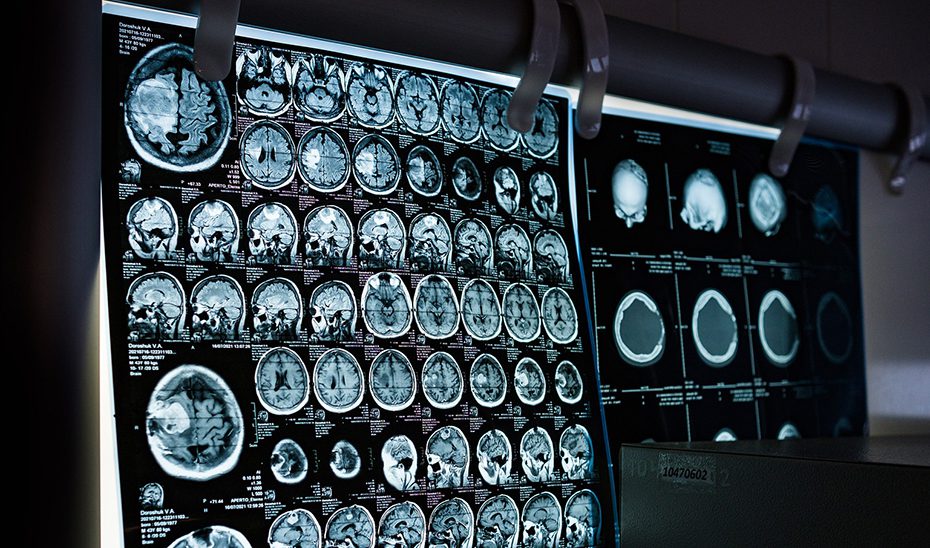

El glioblastoma es un cáncer poco frecuente, con una incidencia estimada entre tres y cinco casos por cada 100.000 habitantes, pero altamente agresivo, con una supervivencia media de 14 a 16 meses, incluso con los mejores tratamientos actuales.